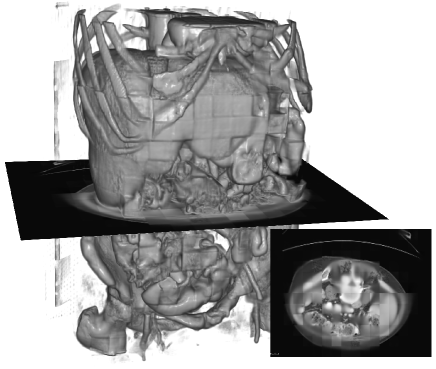

Visualization. We visualize 3D reconstruction results to check what HySparK learns in pre-training. As shown in Fig. 6, our method can almost reconstruct the different shapes of organs, bones, and other details from the very small portion of unmasked patches.

(a)

(b)

(c)

(d)

(e)

(f)